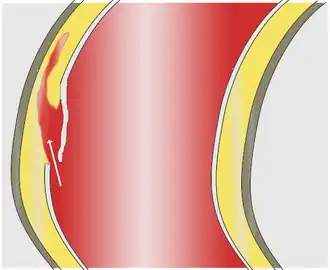

La pared de la aorta está formada por tres capas concéntricas: íntima, media y adventicia. La íntima se encuentra en contacto directo con la sangre y está formada por células endoteliales. La media es mucho más gruesa, está formada por hasta 50 capas concéntricas de láminas de elastina entre las que se intercalan células de músculo liso con capacidad contráctil. La adventicia es la capa más externa, es relativamente fina y está formada por fibroblastos, fibras de colágeno y elásticas.[11]

- Disección aórtica. Es un desgarro de la pared arterial que permite que la sangre fluya entre sus capas y las fuerce a separarse, formando una falsa luz en la pared.[13]

- Ateroesclerosis. Consiste en el depósito de sustancias lipídicas en la capa íntima de la pared arterial.

- Úlcera aórtica penetrante. Consiste en la formación de una ulceración sobre una lesión previa por arterioesclerosis, penetrando en la pared a cierta profundidad.[13]